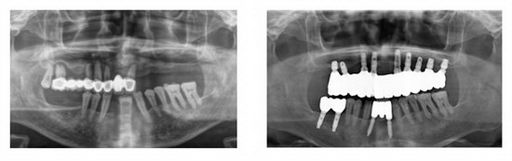

需要注意的是,老年患者的口腔条件比年轻人要复杂的,因为普遍存在牙槽骨的吸收、骨量不足等情况,所以建议选择经验丰富,技术娴熟的种植医生。

Dr.王强,合生齿科医疗主任,现任北京口腔医学会口腔种植学专业委员会专业委员,从事牙齿种植25年,累积牙齿种植7500多颗。

在从事牙齿种植的20多年里,王主任的患者已经遍布全国各地,其中就有不少的老年患者。

最年长的甚至有90多岁。

尽管大多是疑难病例,王主任也凭借着过硬的医术排除各种困难,谨慎设计种植方案,耐心安抚老人的情绪,顺利为他们解决了缺牙问题,并有效减少了治疗过程中的痛苦,获得了老人的认可和肯定。